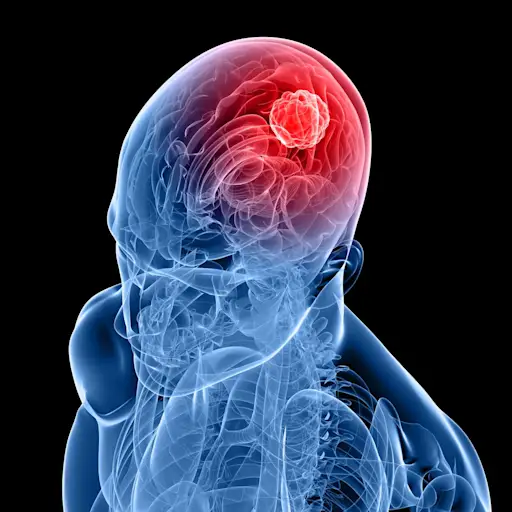

肿瘤

脑瘤,无论是恶性的还是良性的,都可能类似于痴呆,尤其是生长缓慢的肿瘤。脑瘤会干扰大脑功能,也会导致性格的改变。